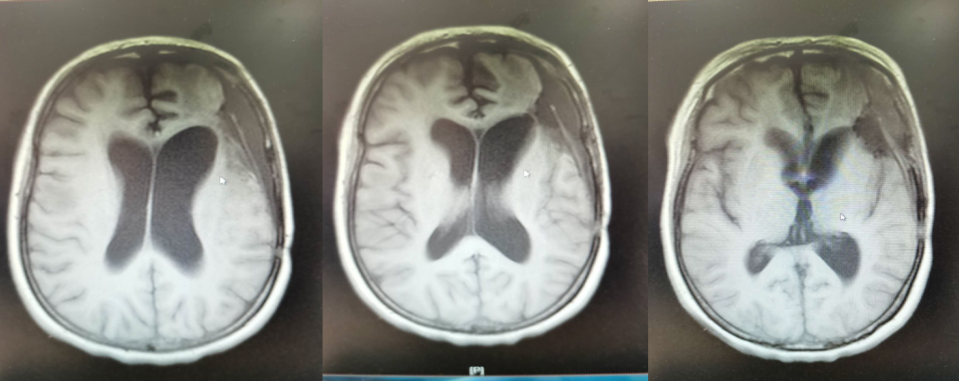

术后半年MRI增强